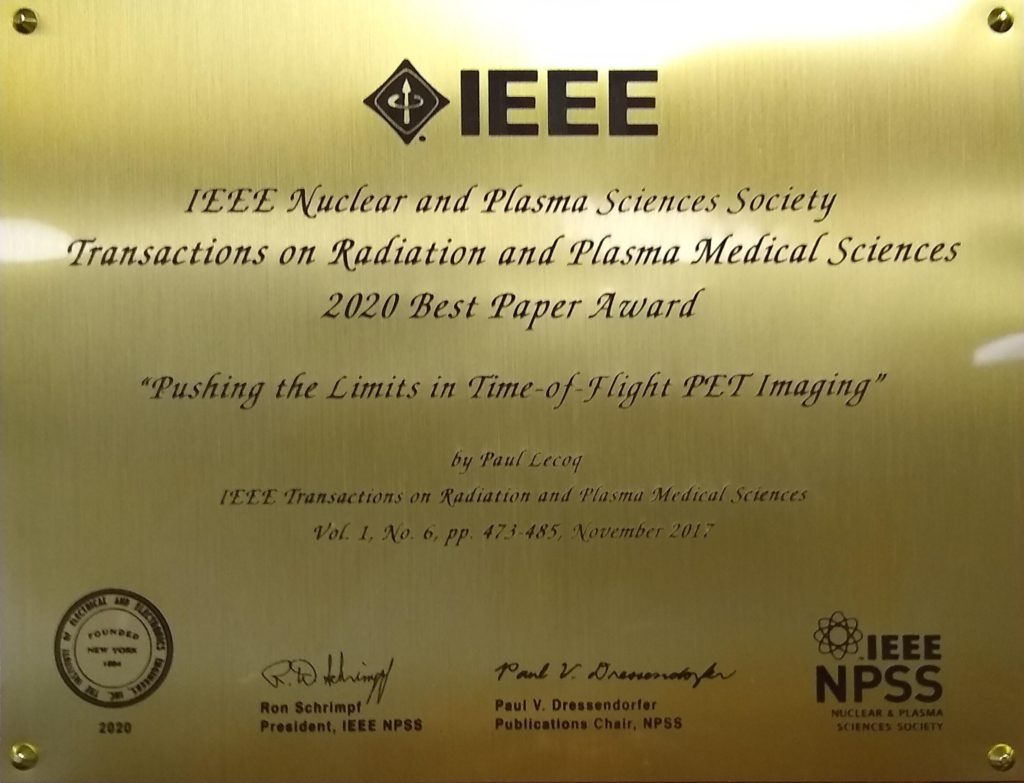

IEEE TRPMS 2020 Best Paper Award

- Paul Lecoq, CERN, Geneva, Switzerland